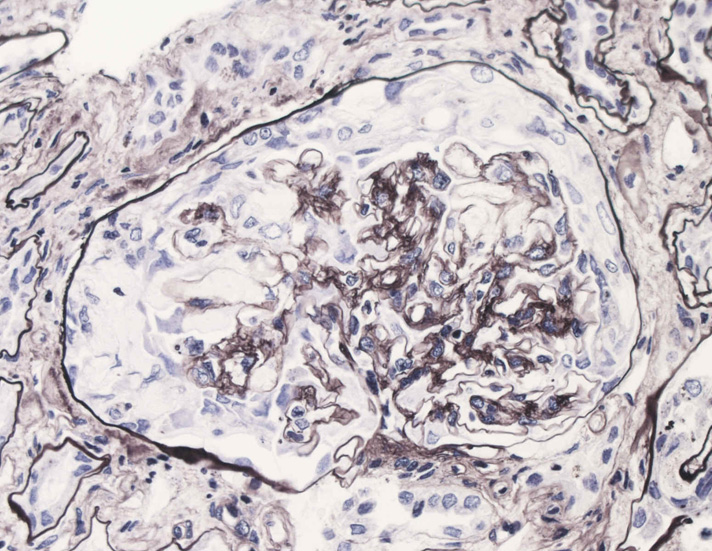

腎臓の病理組織所見-->壊死性糸球体腎炎

kidney04pas.jpg

kidney05.jpg

Fig.03(PAS)Fig.04(PAM染色)Fig.05(PAM染色)